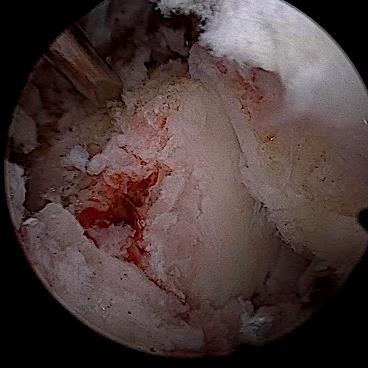

• 经皮经胆道镜激光消融术与光动力疗法治疗胆管黏液性囊性肿瘤的临床疗效及治疗技巧

摘要:目的 探讨经皮经胆道镜激光消融术与光动力疗法(PDT)治疗胆管黏液性囊性肿瘤的临床疗效及治疗技巧。方法 回顾性分析2018年1月-2023年12月该院消化内科收治的13例胆管黏液性囊性肿瘤患者的临床资料,采取经皮经胆道镜激光消融术、PDT治疗或两者联合治疗。观察患者手术相关情况、病灶情况、引流情况、术后6个月生存情况和并发症发生情况。结果 所有患者均顺利完成经皮经胆道镜激光消融、PDT或两者联合治疗,治疗成功率为100%。所有患者术后体温恢复正常。7例患者术后1周内黄疸明显减退,其余6例黄疸虽然未明显减退,但血清总胆红素有所下降或保持稳定。所有患者术后1周内,胆管各分支新生物减少,病灶明显缩小。术后早期(30 d内),所有患者引流管均保持通畅,未发生因肿瘤组织脱落或坏死物堵塞所导致的急性堵管事件。术后引流管留置时间平均为4.2个月。术后6个月,无死亡病例,术后6个月生存率为100%。未发生胆道穿孔和大出血等严重并发症。结论 经皮经胆道镜激光消融术联合PDT治疗胆管黏液性囊性肿瘤,可以缩小病灶范围,缓解胆道梗阻,提高患者生活质量,且并发症少。值得临床推广应用。